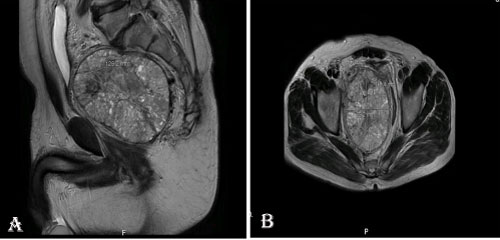

A 61-year-old male patient who presented with dysuria, low back pain and constipation complaints had narrowing of the rectum lumen by rectal digital examination. Colonoscopy showed an external compression to the rectum. Pelvic computed tomography showed a rectangular mass of 110 × 90 mm with a smooth contour in the right lateral side of the sigmoid colon, extending to the pelvis and compressing the prostate gland externally. Magnetic resonance imaging (MRI) revealed a mass of 126 × 119 × 99 mm T1 cross-sections with light hyperintense in the area corresponding to the prostate region, and a solid mass with vascular and fibrotic components showing significant heterogeneous hyperintensity in T2 sections (Figure 1). The totally resected mass was macroscopically well-circumscribed without capsule and was measured as 12 × 10 × 8 cm. The mass was multilobulated and the cross-section was in solid character and gray-white in color. Frequent bleeding and necrosis foci were present (Figure 2A). In the microscopic examination, the tumor was consisted of hypercellular multilobulated areas separated by edematous and hyalinized hypocellular bands. Ischemic necrosis and tumor necrosis areas were observed as large multifocal areas (Figure 2B). A focus of adjacent peripheral soft tissue invasion was noted in the periphery of the tumor (Figure 2C). Tumor stroma showed a vascular pattern in many areas and it was compatible with hemangiopericytoma in some areas while it was reminiscent a hemangiosarcoma in some areas (Figure 2D). Other areas showed vaguely vascular spaces consisting of crossing short bundles of tumor cells in hyalinized stromal areas (patternless pattern) (Figure 2E). Tumor cells had limited spindled cytoplasm and mild elongated plump nuclei with vesicular chromatin pattern (Figure 2F). Mitotic index was high in some areas [mitotic figure; 10/10 in a high power field (HPF)] (Figure 2G). Immunohistochemical analysis revealed a diffuse strong cytoplasmic staining with CD34 and bcl-2, multifocal cytoplasmic staining with EMA and vimentin, focal weakly membranous expression with CD99, diffuse nuclear expression with PAX-8 and STAT6 (Figure 2H, Figure 2I and Figure 2J). No expression was observed with C-kit, PDGFRA, DOG-1, SMA, MSA, desmin, factor-VIIIA, pan-cytokeratin, calretinin, CD10, PSA and S100. The Ki67 index was 10%. The case was evaluated as histopathologically compatible with solitary fibrous tumor with retroperitoneal location. The tumor was evaluated in the malignant category due to widespread necrosis, increased cellularity and high mitotic index. There were no signs of recurrence/metastasis in our case at the 12th postoperative month.

Figure 1: The images of vertical (A) and horizontal (B) plan of a well-circumscribed retroperitoneal solid mass lesion on the pelvic MRI of the patient. View Figure 1